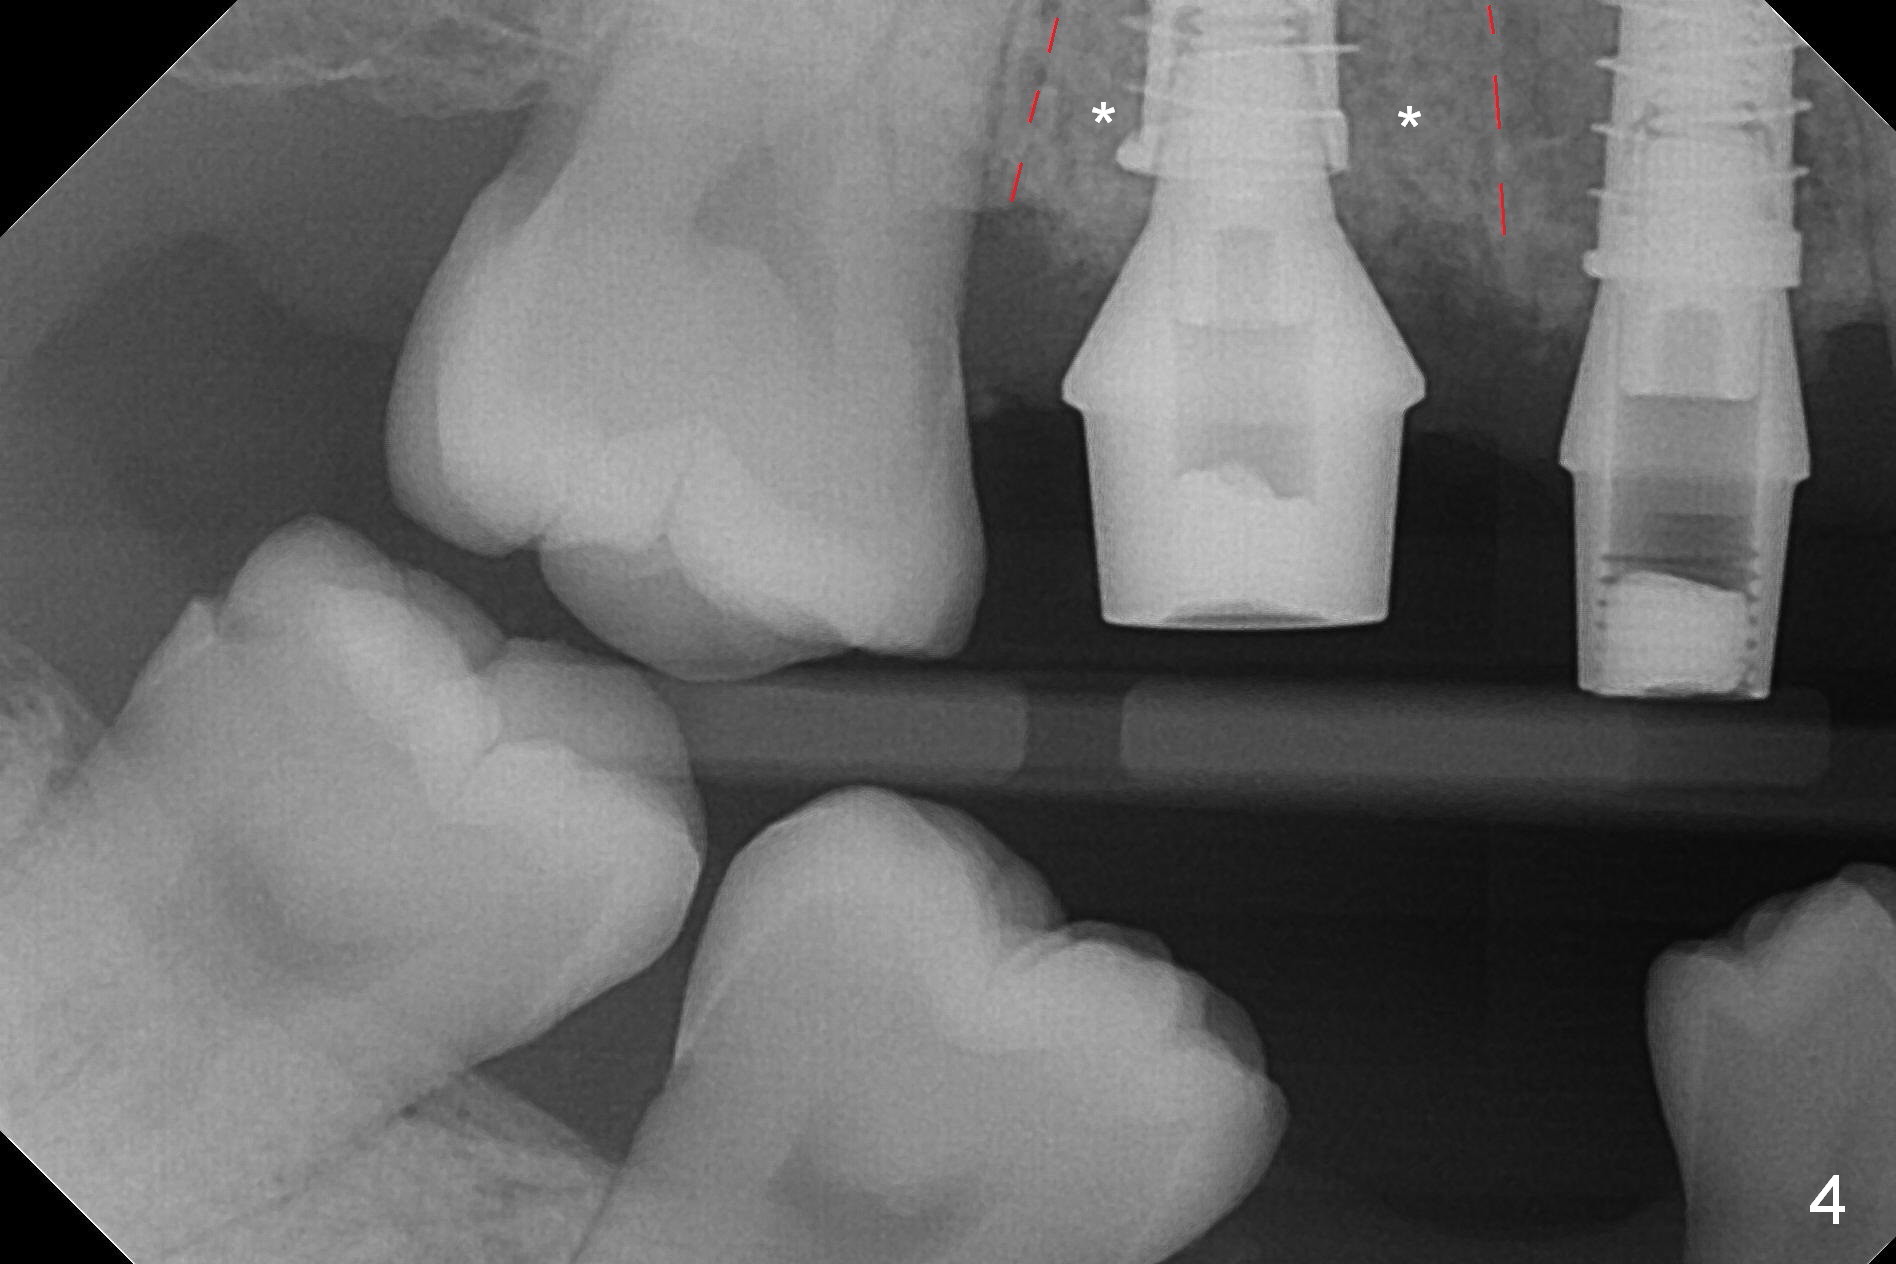

In contrast, osteotomy at #4 is finished with a single MD 3.3 mm. A 4x13 mm implant is placed with more than 50 Ncm. Pair abutments are immediately placed (6.5x4(3) and 4.5x4(3) mm) for splinted immediate provisional. The remaining socket (Fig.4 red dashed line) is filled with mixture of allograft, autogenous bone and Osteogen (*).